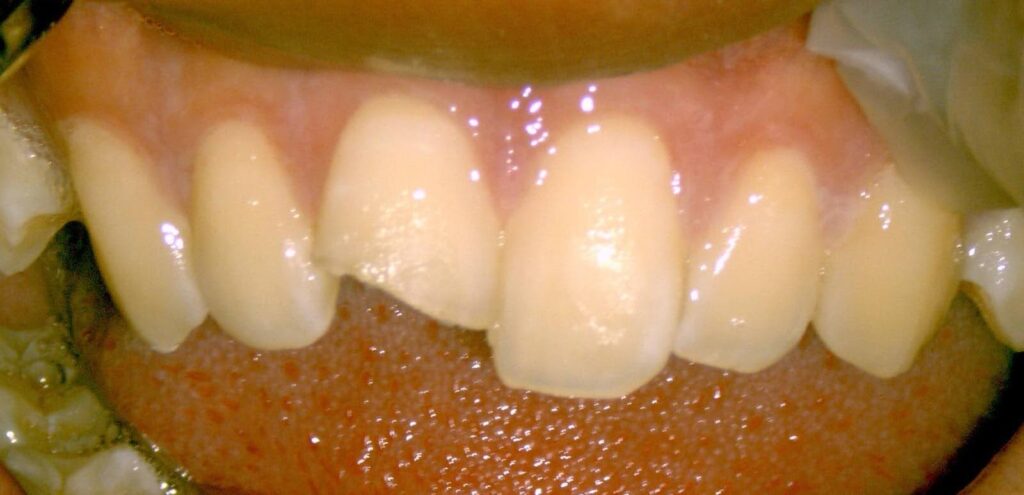

Dr.:麻酔をし、元の位置に引っ張り出して戻し、隣の歯と仮止めします。歯髄(=神経)は傷み残せない状態なので、根管治療をしました。